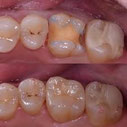

金属の被せものは歯との間に隙間ができやすく、歯としっかり接着しない材料のため、

2次虫歯が多く発生しやすい材料の1つです

一見問題なく入っているように見えても、金属を外してみると中の歯質が虫歯になっていることが多いのです

そのため現在当医院では金属を使用する治療は特別な症例を除いて行っておりません